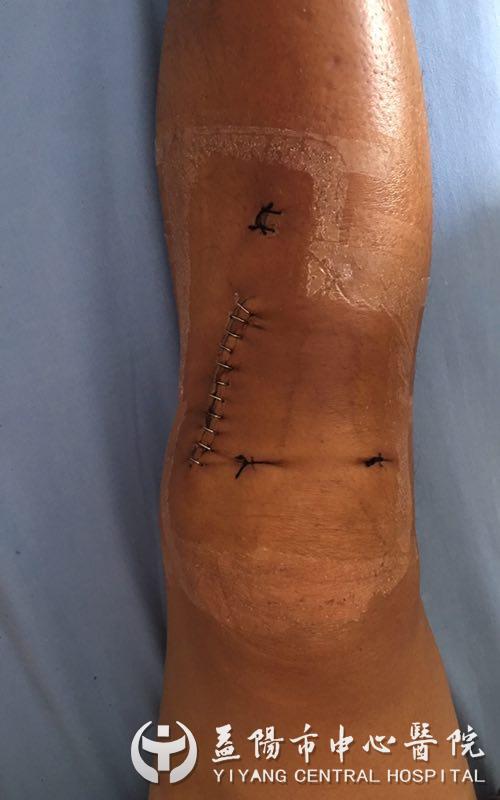

骨外科二病区关节团队考虑到患者日后仍需从事繁重的体力劳动,经过团队反复讨论、研究,决定用3D打印技术辅助下行胫骨高位截骨术。先通过术前在计算机三维模型上精确规划截骨线及骨块复位,并通过计算机软件设计制作能够与胫骨近端骨质的三维形态完全匹配的数字化导板,并通过3D打印技术打印出来,提高手术精确性。完成详细的术前准备后,骨外科二病区关节团队为杨先生实施了手术,手术顺利进行仅耗时三十分钟左右,术后恢复良好,术后第2天就可以在助步器辅助下下地行走。他逢人就夸关节手术技术高、技术强,不仅缓解了疼痛,还保住了他的膝关节。3D打印辅助下胫骨高位截骨术是目前治疗胫骨近端畸形的一种有效手术方法。

膝关节骨性关节炎是中老年常见病、多发病,胫骨截骨矫形术是通过矫正膝内翻畸形,将肢体负重的力线从已经磨损的膝关节一侧转移到另一侧,避免胫骨和股骨关节软骨之间的摩擦而引发的疼痛,降低胫骨内压,改善关节功能,减轻疼痛,延缓关节炎进展,使退变的关节软骨得到部分修复,从而使临床症状消失或减轻。结合3D打印技术设计截骨导板,可以使手术方案个体化,截骨精准,大大缩短了手术时间,也降低了手术风险。这次手术的成功,代表着益阳市中心医院关节团队水平在省内又向前迈进一步,同时意味着保膝“一条龙”治疗——从腓骨高位截骨术→胫骨高位截骨术→单髁置换术→全膝关节置换术全线贯通,让患者根据不同年龄不同病情不同经济状况,有了更多治疗方案选择。(杨瑞琪)